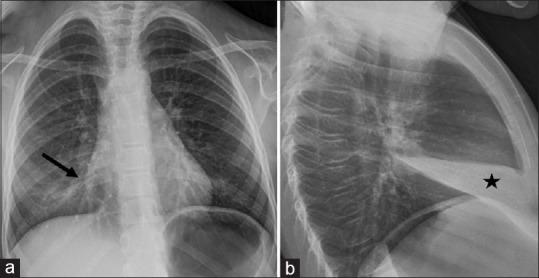

儿童间质性肺疾病:基于病例的影像学表现综述

Childhood interstitial lung disease: A case-based review of the imaging findings.

Childhood interstitial lung disease (chILD) consists of a large, heterogeneous group of individually rare disorders. chILD demonstrates major differences in disease etiology, natural history, and management when compared with the adult group. It occurs primarily secondary to an underlying developmental or genetic abnormality affecting the growth and maturity of the pediatric lung. They present with different clinical, radiologic, and pathologic features. In this pictorial review article, we will divide chILD into those more prevalent in infancy and those not specific to infancy. We will use a case based approach to discuss relevant imaging findings including modalities such as radiograph and computed tomography in a wide variety of pathologies.

摘要

儿童间质性肺疾病(chILD)由一大组种类繁多、各自罕见的疾病组成。与成人组相比,chILD在疾病病因、自然史和治疗方面存在重大差异。它主要继发于影响小儿肺部生长和成熟的潜在发育或基因异常。它们具有不同的临床、放射学和病理学特征。在这篇图片综述文章中,我们将把chILD分为在婴儿期更常见的疾病和并非婴儿期特有的疾病。我们将采用基于病例的方法来讨论相关的影像学表现,包括在各种病理情况下的X线片和计算机断层扫描等检查方式。